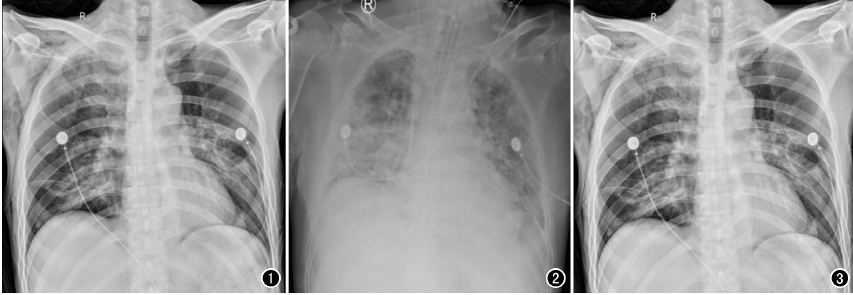

必一运动科技最新一代移动DR—飞燕Ⅱ,是国内首款大尺寸100微米超高清成像移动DR设备,具有1800万像素的超高分辨率,让床旁摄影的影像质量全面迈入高清时代。图像质量不仅远超当前市场上的移动DR设备,也远超过当前大部分固定DR设备的图像质量。

相较于普通DR的百万摄影像素,近2000万的高清像素,可以极大的提升床旁检查效率,包括骨科、新生儿科、心脏外科、重症监护科、急诊科等患者的快速检查。相较于目前市面上的低像素移动DR设备,100微米平板移动DR,在图像的分辨率、宽容度上都全面优于常规的130微米左右的移动DR设备。

以心脏手术为例,开胸心脏手术多数是在低温、全麻和体外循环下进行,胸腔创伤较大、风险极高,心脏术后,心外科医师为了能及时了解术后患者的双肺复张情况、气管插管导管头端位置以及手术并发症等情况,需要及时对患者进行胸部X线片检查,以便观察气管插管位置,一般来说,插管位置下端应位于第3胸椎水平,过深或者过浅都将影响呼吸机的辅助效果,应确保位置准确,以免影响通气状况。另外,包括对于相关手术并发症的检查,包括:胸腔积液、气胸、肺不张等常见问题,需要及时进行胸部X光检查。相较于几百万像素的移动DR,百微移动DR,在图像质量上显示更清晰,检查效率更高,更利于医生及时进行处置。